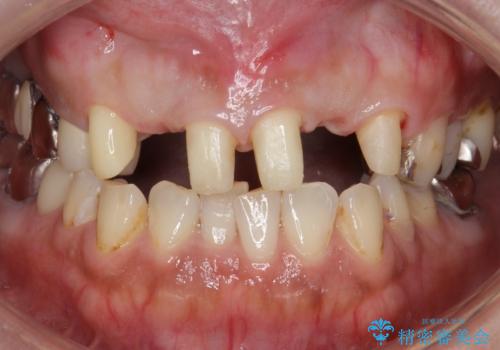

②左右2番の歯を抜歯してブリッジの被せ物を入れる(矯正ほど費用、時間はかからない)

②の方を選択されましたので被せ物治療を行いました。

最終的な被せ物は抜歯を行なってから半年経ってから形を整えて型取りを行います。